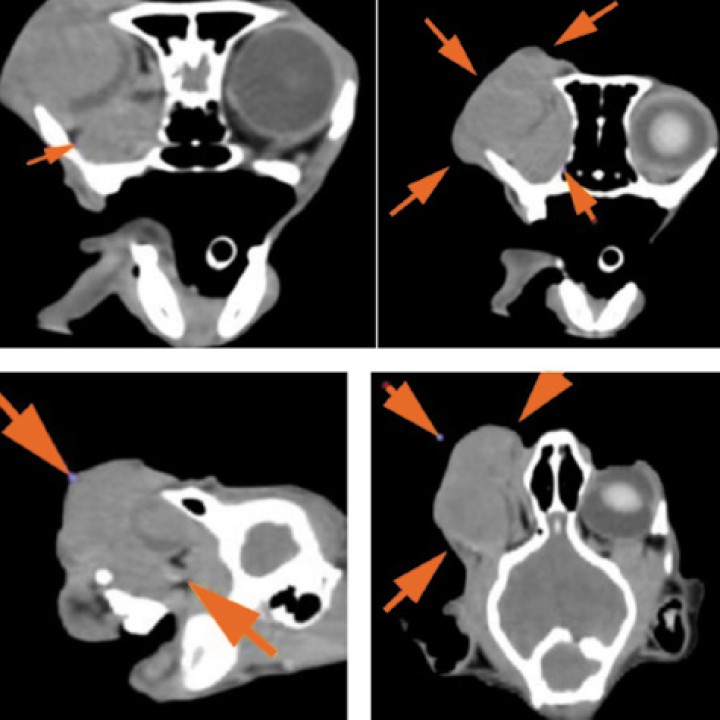

Finalmente, se realizó una tomografía computarizada (TC) de cabeza y tórax con el objetivo de identificar posibles metástasis regionales o a distancia, así como para facilitar una adecuada planificación quirúrgica. La TC no evidenció lesiones osteolíticas, linfadenopatías ni signos de diseminación metastásica, incluido el sistema nervioso central. Sin embargo, no fue posible descartar con certeza la invasión del nervio óptico, ya que la masa ocupaba por completo la cuenca orbitaria derecha, incluyendo el espacio retrobulbar y desplazando los vasos sanguíneos en dirección dorsocraneal. Esta extensión dificultó la evaluación precisa de la infiltración del nervio óptico y estructuras vasculares adyacentes. A pesar de ello, los hallazgos confirmaron la localización primaria de la masa en la región ocular derecha y la ausencia de diseminación a otros órganos en el momento del estudio (Figs. 3 y 4).

Imágenes tomográficas (transversal, sagital y coronal) donde se observa la masa de 3,3 × 3,7 × 5 cm (flechas) centrada en el globo ocular derecho, con atenuación de partes blandas y escasa captación periférica de contraste, que ocupa toda la órbita incluyendo el espacio retrobulbar, desplazando estructuras vasculares y con posible invasión del nervio óptico. Se extiende hacia el exterior sin provocar lesiones óseas en las estructuras adyacentes. Imagen cedida por el Hospital Bluecare.